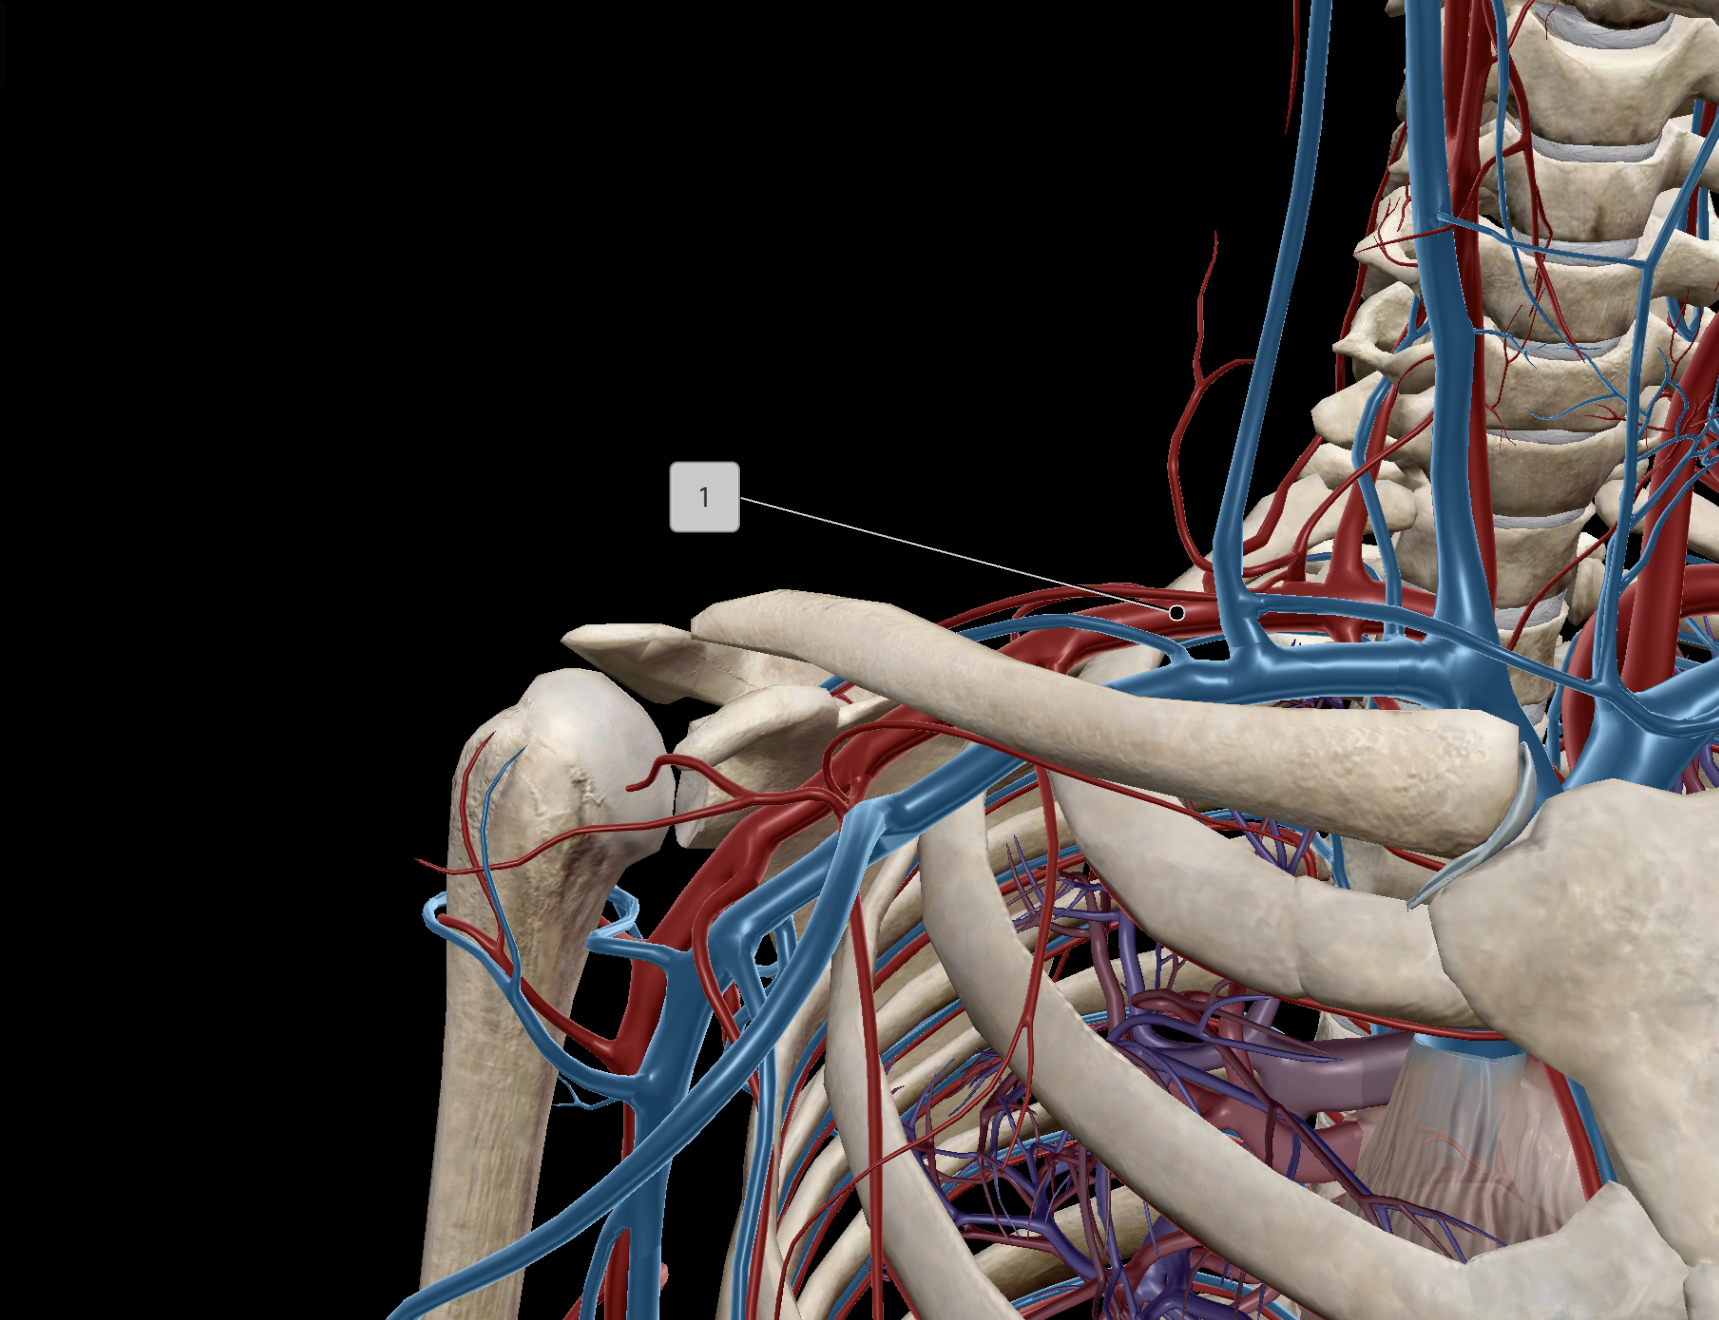

Subclavian Artery

Axillary Artery

Axillary Vein

Subclavian Vein